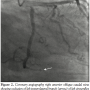

ng/mL), but subsequent tests revealed increased levels of cardiac enzymes (troponin I 5.23 ng/mL, creatinine kinase 59.8 ng/mL, myoglobin 266 ng/mL). Electrocardiogram revealed ST segment elevation in leads II, III, and aVF with reciprocal changes in leads I and aVL. The patient was emergently transferred for catheterization, which revealed 100% stenosis of left posterolateral branch of left circumflex artery (Figures 1 and 2). Other coronary arteries were clean. Percutaneous transluminal

coronary angioplasty was unsuccessful with no improvement of blood flow after first balloon inflation. The lucency in the obstruction with abrupt cut-off, which is an angiographic feature of embolism, pointed to a primary embolic event. The patient became hypoxemic and bedside echocardiography was performed to rule out right ventricular strain due to pulmonary embolus. Echocardiography revealed mild inferolateral hypokinesis and a large, soft-tissue mass partially filling the left atrial cavity with partial obstruction of mitral orifice by a tumor, causing moderate mitral

Discussion. Coronary atherosclerotic disease is the most common pathology leading to myocardial infarction. Other rarer causes include congenital coronary artery anomalies, inflammatory diseases of coronary arteries, dissection of aorta, metabolic disorders, coronary spasm, myocardial contusion, and emboli to coronary artery. These emboli may be paradoxical emboli or originate from cardiac tumors, left heart thrombi, infective endocarditis, or prosthetic valves.1 Our patient presented with acute myocardial infarction due to occlusion of the posterolateral branch of the left circumflex artery. Splenic infarct suggested probable embolic phenomenon. Along with detection of the left atrial sarcoma and angiographic findings, this points to coronary emboli as the most likely cause of myocardial infarction. Hypoxemia in our patient was probably precipitated by tachycardia in the setting of moderate mitral stenosis.